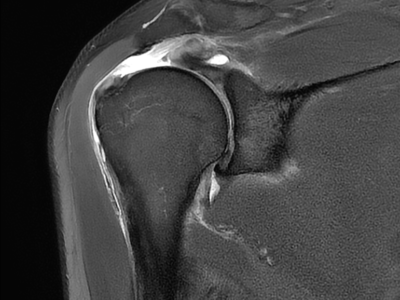

Rotator Cuff Tear

Minimally Invasive Arthroscopy – Small incisions (less than 1cm) for faster recovery and minimal scarring

Common Procedures – Rotator cuff repair. capsular release (for frozen shoulder). calcium removal. labral repair. fracture fixation. etc.